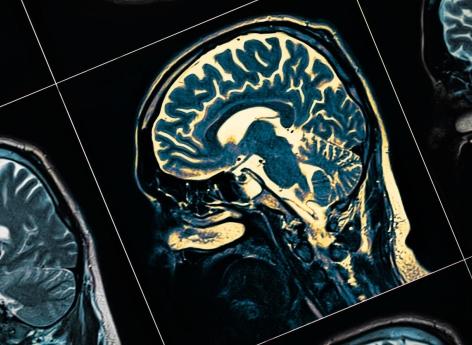

- sudok1/istock